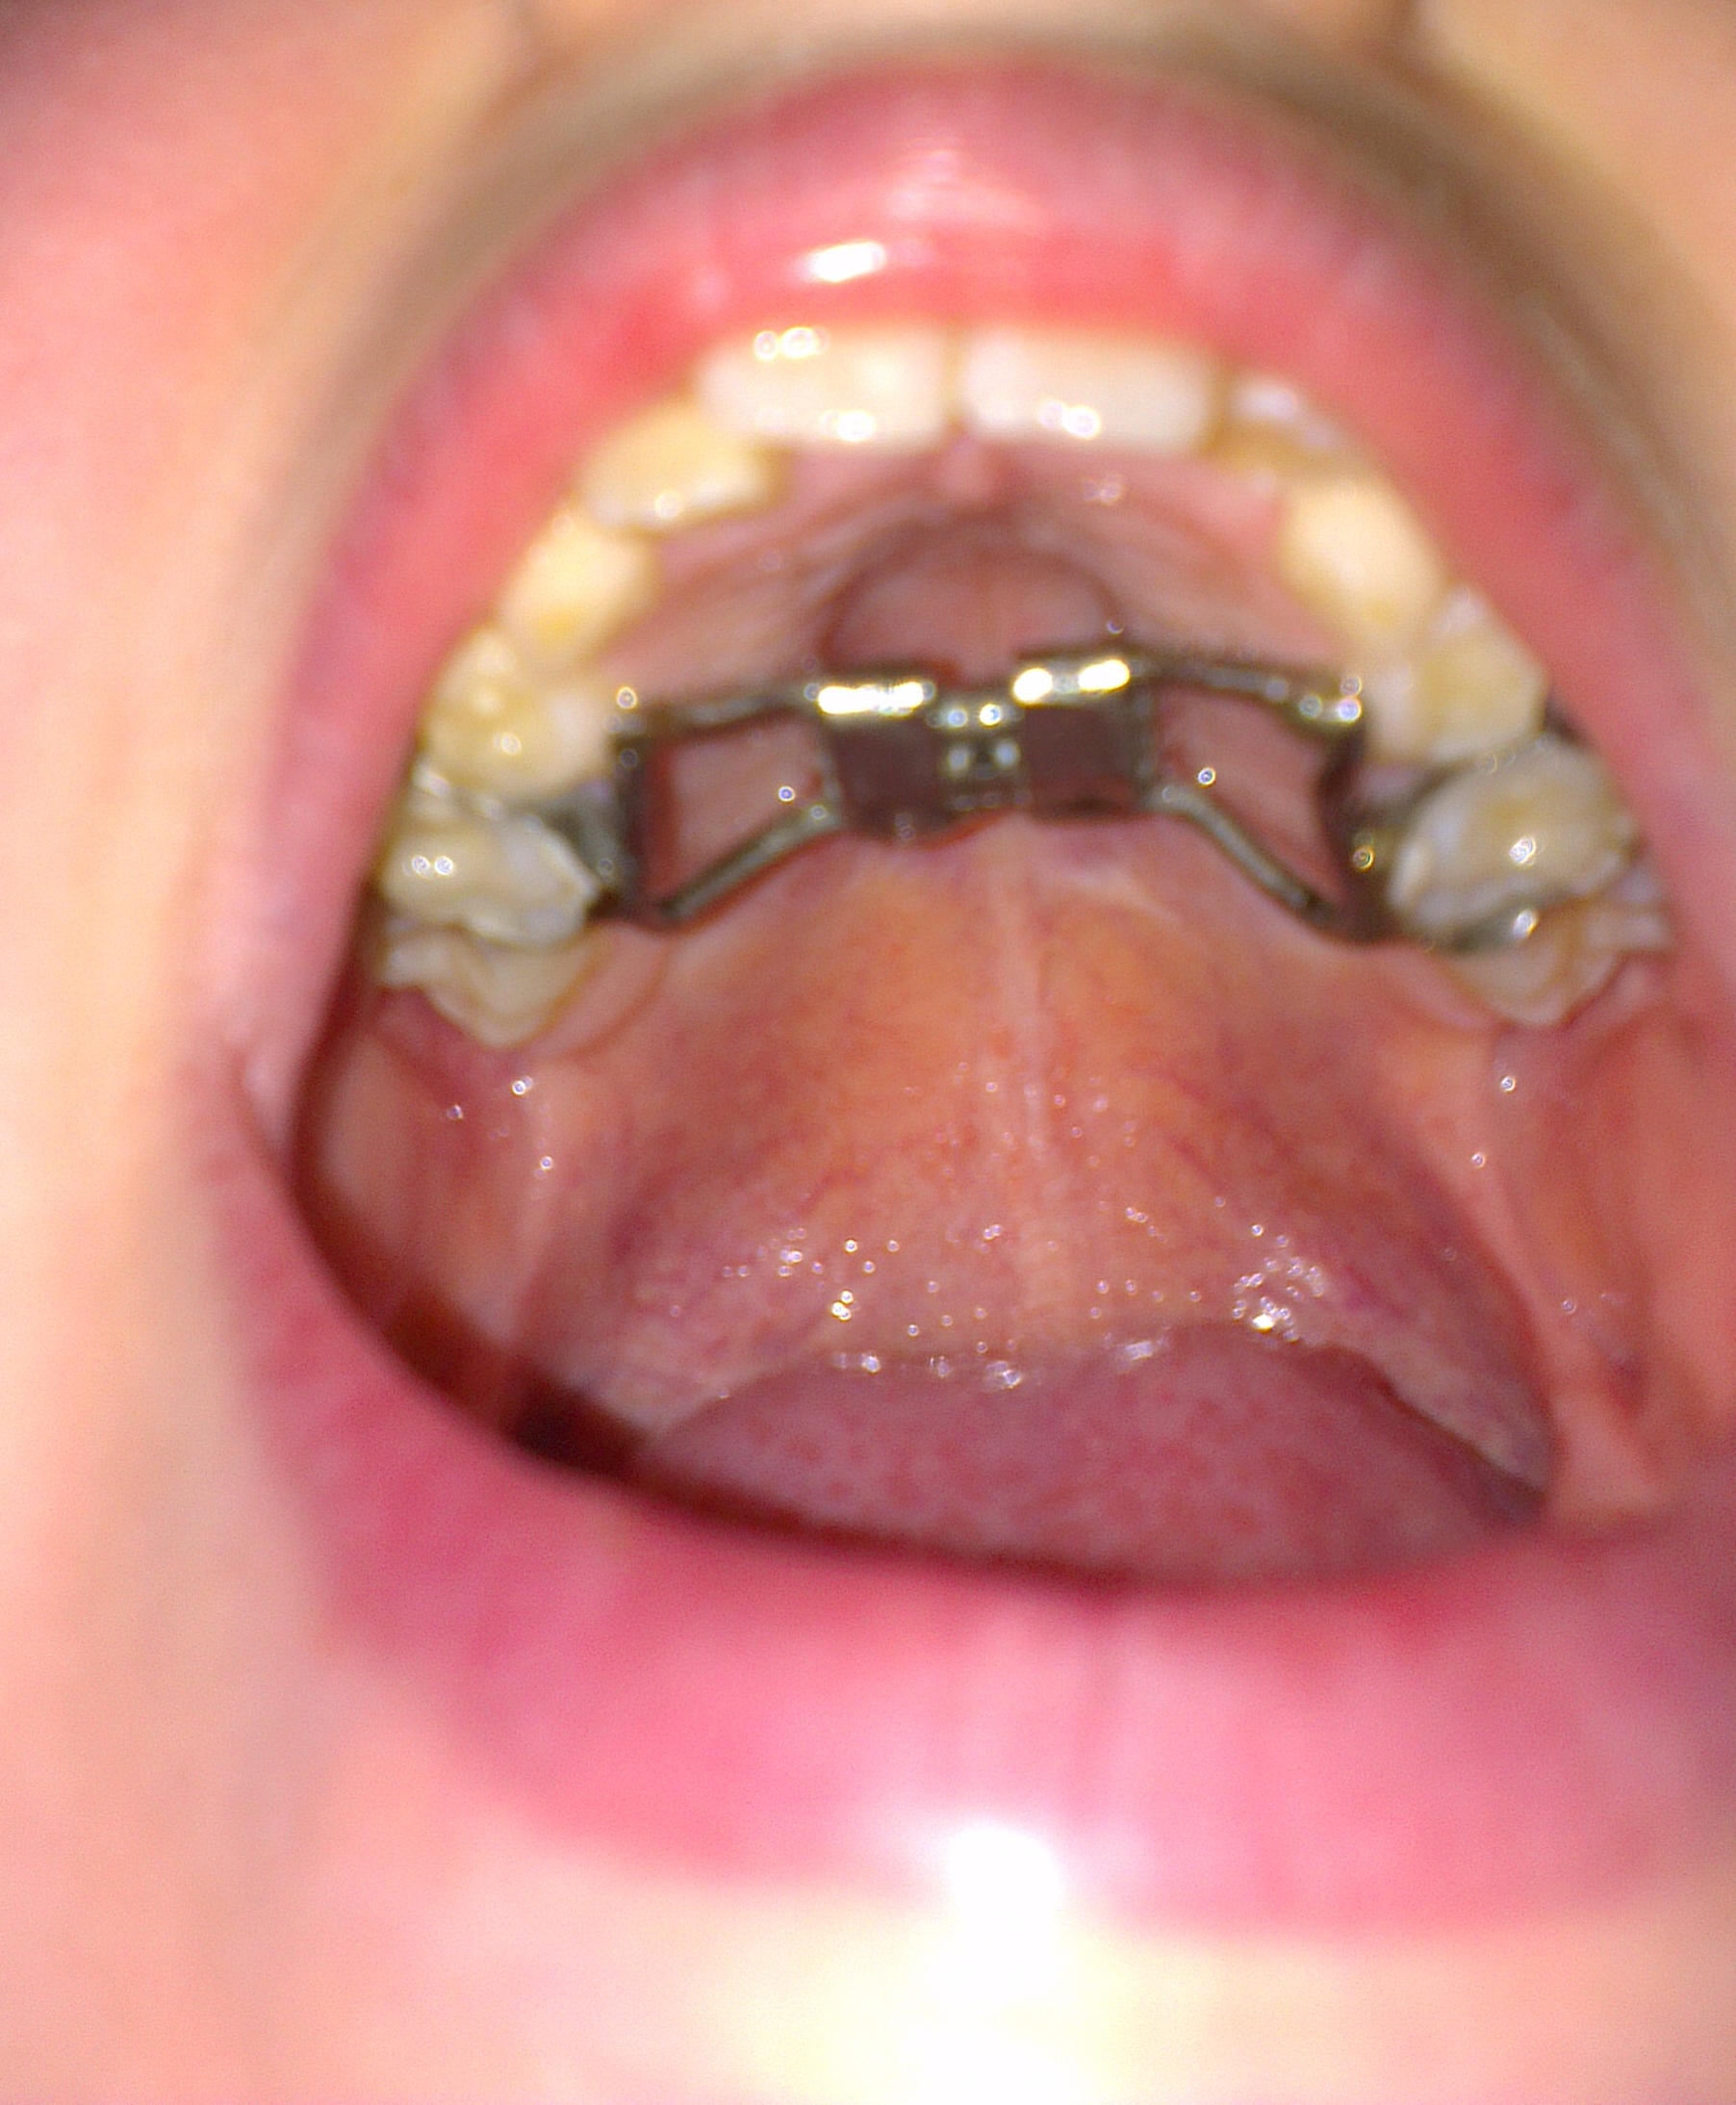

Ho un bambino di otto anni che dallo scorso settembre ha un espansore palatale fisso

Salve, ho un bambino di otto anni che dallo scorso settembre ha un espansore palatale fisso cementato sui sesti, non ha mai avuto nessun tipo di problema si è adattato bene solo che quest'apparecchio si stacca di continuo. Allora mi chiedo se ha senso continuare a metterlo perchè credo che non faccia il suo effetto essendo che

A mia figlia di 8 anni è stato applicato un espansore palatale

Buonasera. A mia figlia di 8 anni è stato applicato un espansore palatale sui 5 perché i 6 non sono ancora scesi del tutto. La dottoressa ha dato 2 giri il giorno dell'applicazione dell'apparecchio e noi ne diamo uno al giorno. A distanza di 6 giorni non si vede ancora lo spazio tra i centrali. È normale? È

Alla mia bambina di 8 anni è stato applicato un espansore palatale

Alla mia bambina di 8 anni è stato applicato un espansore palatale con istruzioni di dare un giro ogni sera per tre settimane dopodichè si era giunti all'espansione voluta dall'ortodontista ed era il 26 novembre 2012, adesso mi hanno comunicato la data in cui verrà rimosso cioè il 18 marzo 2013. Mi chiedo se può